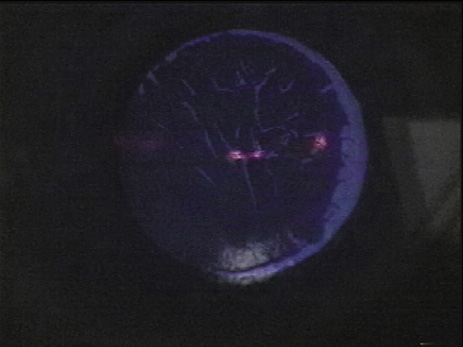

The fragments ejected from the corneal surface are visible several hundred nanoseconds after the laser exposure. For 193-nm irradiation, the particles travel at an initial velocity of approximately 400 m/sec for the first 500 nsec, but then rapidly decelerate. The ejection of the particles ends within 5 to 15 νsec as the decelerating particles form a mushroom-shaped cloud (Fig. 2). 40 Increased exposure energy leads to increases in both the plume size and initial velocity of the ejected fragments. Analysis of the plume has identified numerous molecules that contain between 10 and 20 carbon atoms.41

Fig. 2. Ablation plume created by 193-nm excimer pulse at 900 mJ/cm2 per pulse. High-speed photograph obtained by illumination with Nd:YAG laser at 532 nm 50 msec after the excimer pulse struck the corneal surface (original magnification ×4.5). (Puliafito CA, Stern D, Krueger RR, et al: High-speed photography of the excimer laser ablation of the cornea. Arch Ophthalmol 105:1255, 1987)